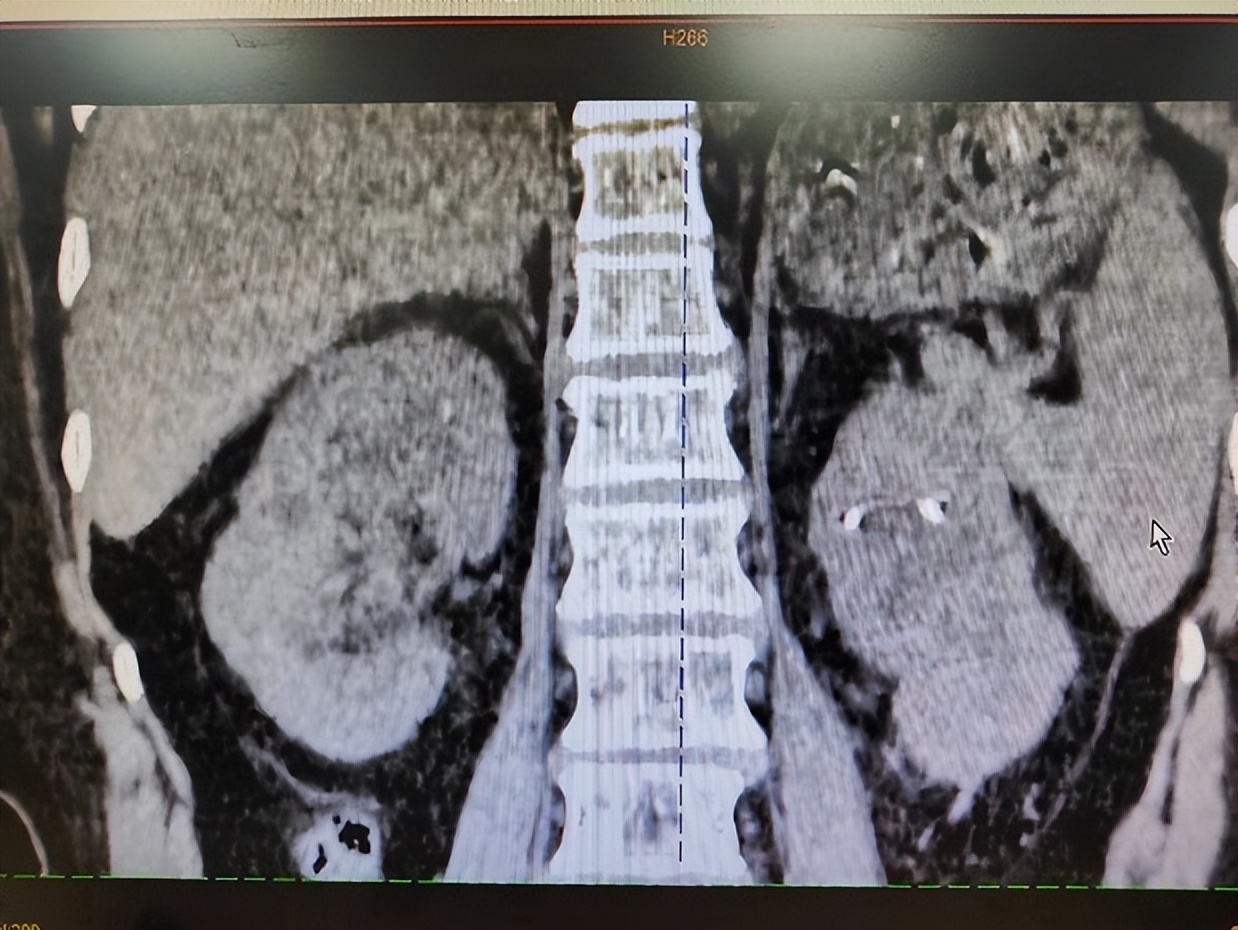

抱着赌一把的心态,患者及家属来找到了黄耀,完善CT等检查后发现,患者双肾柱形结石,两边均超过8cm,每个肾盏都塞满了结石。“我们团队经过讨论后,建议先进行一侧经皮肾镜碎石手术,但是患者结石太大太多,难以取尽,告知患者及家属后,他们虽有诸多疑虑,但还是同意了手术方案。”黄耀回忆道,这个手术采用的多通道模式,最后顺利完成了,将患者大部分结石清除。

桂林医学院第二附属医院在桂林市率先开展“通过输尿管软镜配合可弯曲负压吸引输尿管软镜鞘钬激光碎石取石技术”。该技术利用人体天然的泌尿系统腔道,不在身体上做任何切口,是真正意义上的微创或无创手术。

征得患者及家属同意后,黄耀运用该技术为患者即刻清除了该侧肾脏剩余的全部结石,真正做到了结石基本无残留。经过该侧肾脏成功的手术,也取得了患者及家属充分的信任,在其恢复后又用同种方法行了对侧肾结石手术,同样也取得了很满意的效果。